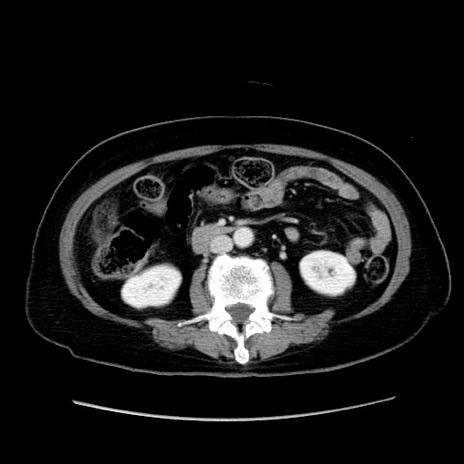

症例19(横断像)

【症例】80歳代女性

【主訴】下腹部痛

【現病歴】約8時間前より下腹部痛の出現あり、救急外来受診。

【既往歴】両側付属器切除

【身体所見】意識清明、下腹部正中に手術痕あり、その部位に一致して圧痛と反跳痛あり。腸蠕動音は亢進。

【データ】WBC 9300、CRP 0.15